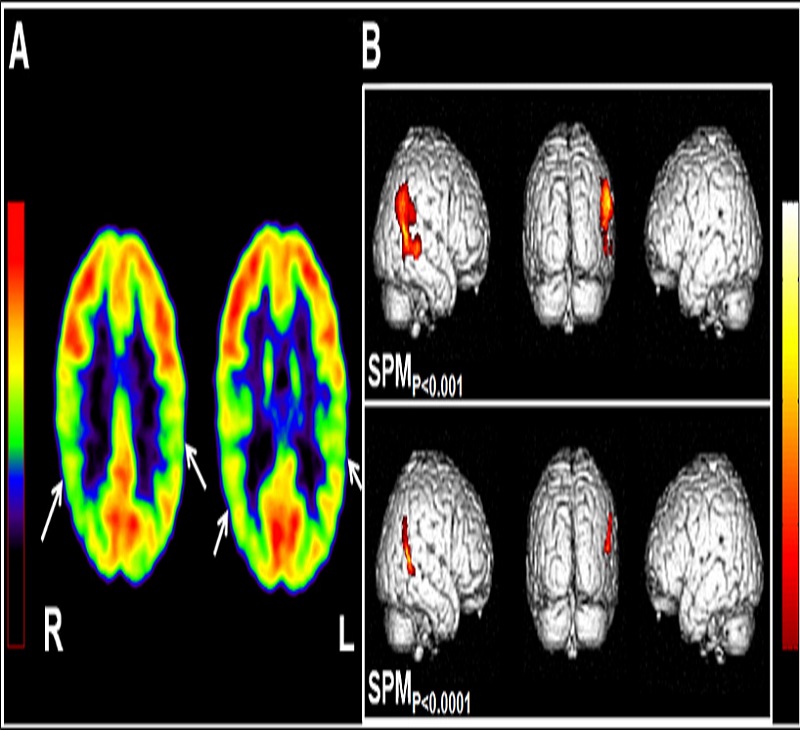

خدمات نقشه برداری از مغز